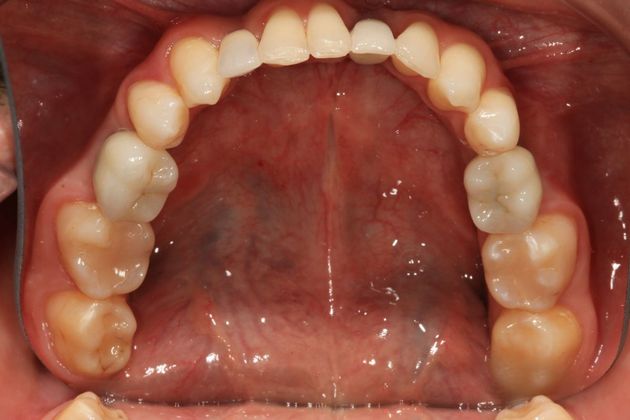

Full mouth rehabilitation. This 20 year old patient had emigrated from Bosnia only a few years earlier with his mother and two sisters after his father had perished in the Bosnian/Serbian conflict. He had severe hereditary dental dysplasia, with multiple retained baby teeth where permanent teeth never formed. He had a total of nine missing teeth, and the teeth that were present were not in their correct positions, leading to a poor bite relationship and multiple large gaps throughout his mouth. He was embarrassed to smile and wanted to know what could be done. His was a very complex case requiring Smile design and; the services of an oral surgeon to take out the baby teeth and strategically place implants at different times of his treatment, an orthodontist to level, straighten and create the proper size spaces for the placement of nine implants, gum sculpting, whitening, and the placement of fillings and crowns on natural teeth, and crowns on the nine implants. It took some time, but he got a great result and the resulting confidence has helped him go to college, get a better job and have a social life! Procedures: Smile design, oral surgery and implant placement, orthodontics, gum lift, whitening, fillings and crowns. TESTIMONIAL:" Dr. Balloch is a very skilled, compassionate and empathetic dentist who develops a personal relationship with his patients. He is (by far) the best dentist that I have experienced in my 85 years. His dental and office staff are equally friendly and professional. Dr.Balloch definitely exceeded my expectations. I highly recommend!"